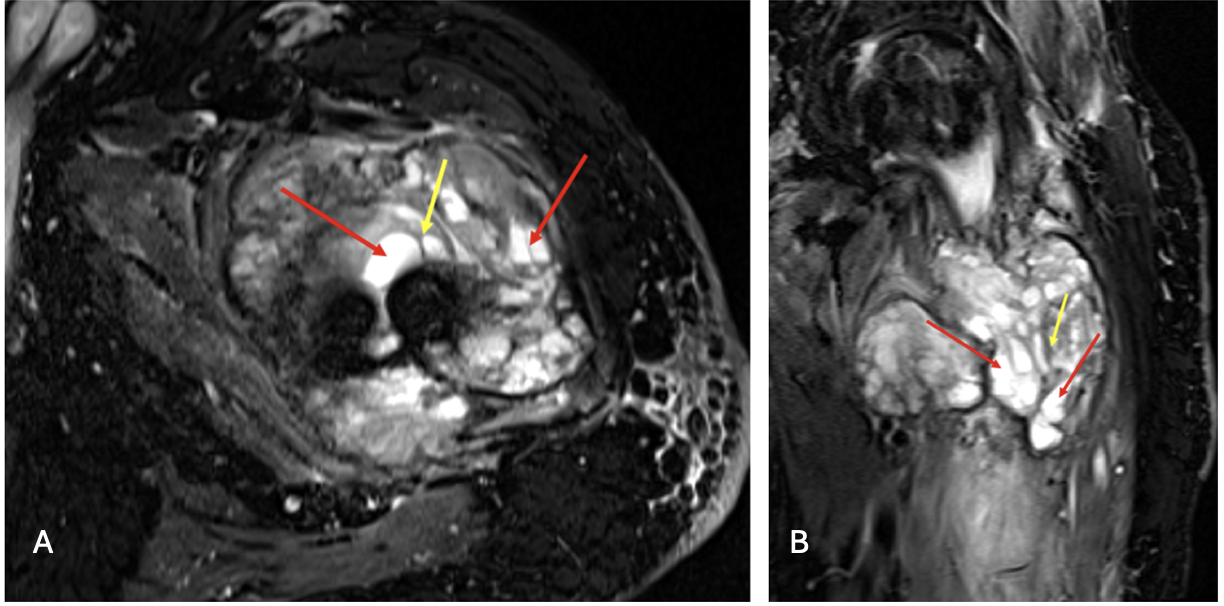

In July 2024, a follow-up magnetic resonance imaging (MRI) revealed a multilobulated destructive mass with hemorrhagic, cystic, and solid extraosseous components (Figure 4).2 The lesion extended into the femoral neck and proximal diaphysis, with T2-hyperintense cystic regions and internal septations.3 At this time, repeat biopsies showed a low-grade giant cell rich neoplasm.

Figure 4A-B. MRI STIR WARP axial (a) and coronal (b) images of the left femur. Heterogeneous, multilobulated soft tissue mass at the fracture site with osseous involvement of the femoral neck, intertrochanteric region, and proximal diaphysis. Internal low-signal septations (yellow arrow) and T2-hyperintense cystic components (red arrows) are present, compatible with a giant cell–rich fibro-osseous neoplasm. New mass consistent with biopsy proven low giant cell rich neoplasm with GNAS mutation.